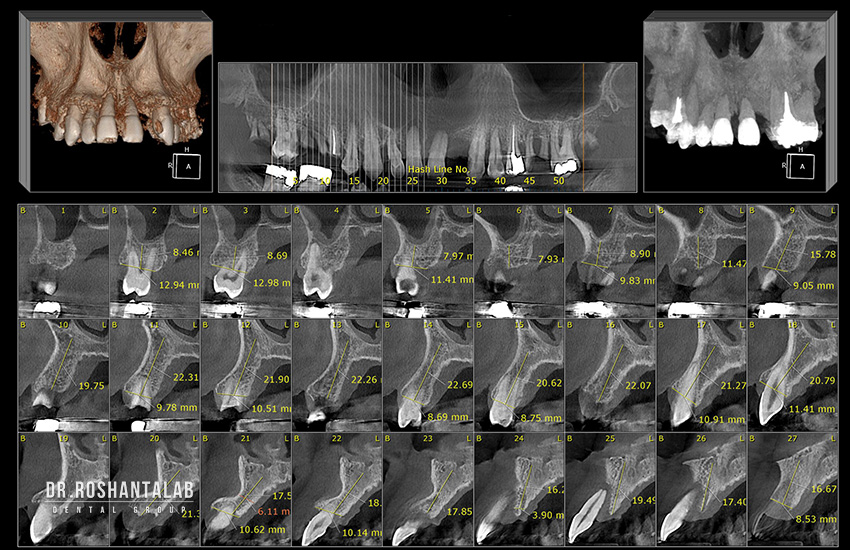

ایمپلنت دیجیتال روشی نوآورانه در دندانپزشکی است که از فناوریهای دیجیتال برای برنامهریزی، طراحی و اجرای کاشت ایمپلنت استفاده میکند. این روش شامل تصویربرداری سهبعدی (CBCT)، اسکنرهای داخل دهانی، نرمافزارهای طراحی کامپیوتری (CAD/CAM) و چاپگرهای سهبعدی است. برخلاف ایمپلنت سنتی که به تصاویر دوبعدی و روشهای دستی وابسته بود، ایمپلنت دیجیتال کل فرآیند را خودکار، دقیق و قابل پیشبینی میکند.

- مشاوره و اسکن CBCT:

بیمار با اسکن سهبعدی (CBCT) بررسی میشود. این اسکن در ۱۵ ثانیه تصاویری دقیق از فک، عصبها و تراکم استخوان ارائه میدهد. - برنامهریزی دیجیتال:

- اسکن CBCT: تصویربرداری سهبعدی با دقت بالا.